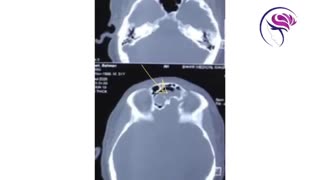

پخش صدا موکوسل آپاندیس اشتراکگذاری لیست پخش ۰ نظر ۰ نظر گزارش تخلف بیشتر گزینههای بیشتر لیست پخش لایکها گزارش تخلف ۰ لایک دکترشهرام نظری منتشر شده در تاریخ ۱۳۹۵/۰۸/۲۲ این کانال دنبال شد دنبال کردهاید دنبال کردن این کانال دنبال کردن جراحی لاپاروسکوپی برداشت یک موکوسل بسیار بزرگ آپاندیس توسط دکتر شهرام نظری. ادامه علم و فن آوری نظرات لبخند لبخند لغو ثبت نظری برای نمایش وجود ندارد.